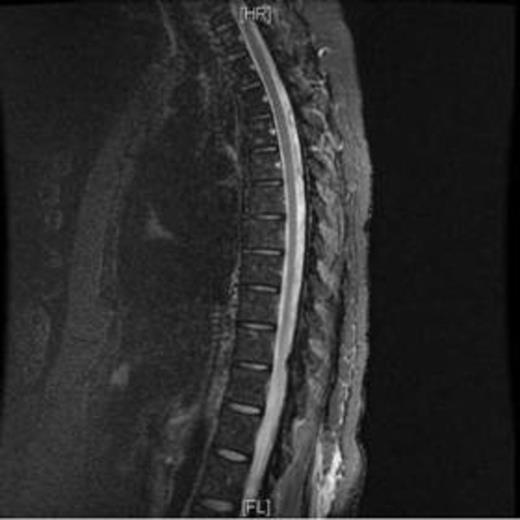

Leptomeningeal reinforcement as seen in MRI.